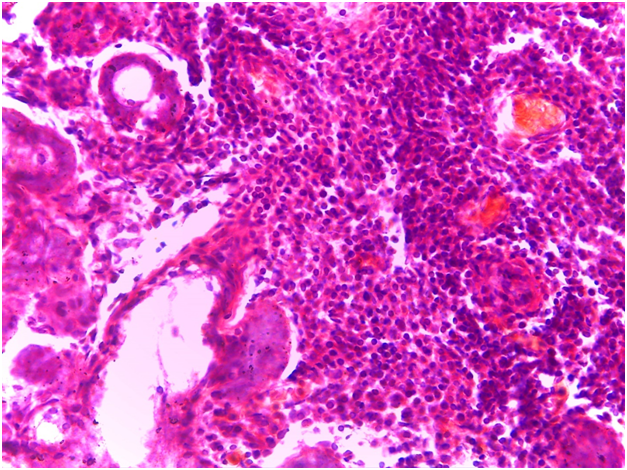

Oral ulcers, especially of the labial mucosa and tongue (Figure 1), were the commonest oral find in GBS while labial numbness, especially in the lower lip, enlarged major salivary glands, and xerotomia were very characteristic of SS. The commonest ocular manifestation in GBS, on the one hand, was intermittent uveitis whose severity ranged from mild to severe while cases of SS have presented typically xerophthalmia. No blindness was reported in the interval of the study as regards cases of GBS. Analogously, no cases of SS did run a transformation course into lymphoma or any other malignancy. Neuro-Behçet involvement and brain aneurysms in GBS, on the one hand, and the follow-up of SS cases, on the other hand, were assessed periodically by MRI. Normal images were obtained in the eighteen cases for this 3-year-old study (Table 1). Sonographically, superficial structures of the head and neck in GBS and SS were assessed. For cases of GBS, a single case has shown a subacute atherosclerosis in the carotid artery but no salient glandular changes were sonographically evident. However, cases of SS revealed a glandular parenchyma of heterogeneous echopattern. There were unmistakable bilaterlal diffuse miliary cystic cavities with patchy calcifications, spotting the underlying atrophic parenchyma. This has overtly promoted a “honeycomb” appearance on the sonograph. No other salient finding could be accentuated (Figure 2).

Figure 2 Sonographic view of parotid gland in SS which displays a heterogeneous parenchyma. The glandular parenchyma exhibits hypoechoic lesions (cystic cavitation) and some calcification foci.There is a conspicuous increase in vascularity on Doppler interrogation.